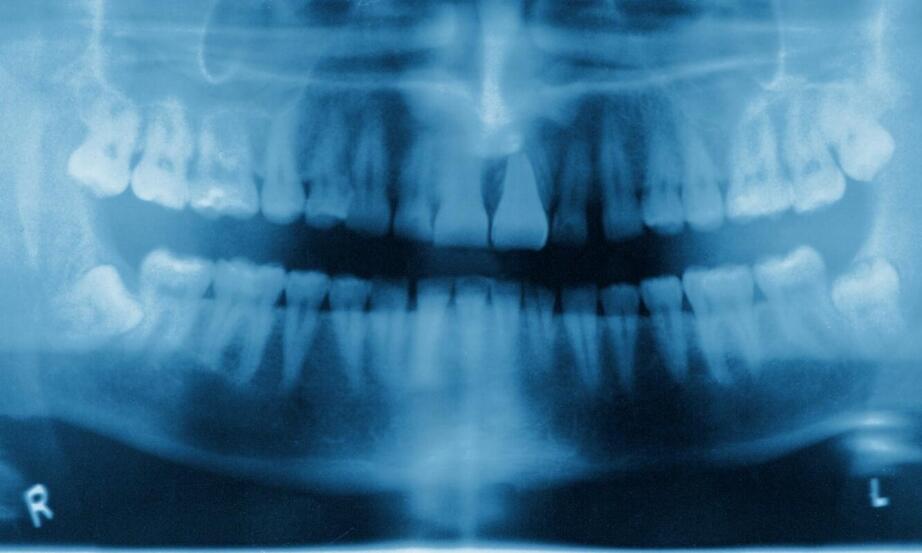

Wykonanie zdjęcia RTG zębów to kluczowy etap w diagnostyce stomatologicznej. Precyzyjne obrazy są niezbędne do planowania skutecznego leczenia, co podkreśla znaczenie tego procesu dla zdrowia jamy ustnej pacjentów. W artykule omówimy kolejne kroki realizacji RTG zębów w gabinecie stomatologicznym, zwracając uwagę na nowoczesne technologie oraz metody stosowane przez specjalistów, które zapewniają najwyższą jakość usług diagnostycznych.

Kolejnym etapem jest właściwe wykonanie zdjęcia rtg zębów we Wrocławiu, co ma kluczowe znaczenie dla dalszej diagnostyki. Stomatolog lub technik radiologiczny ustawia pacjenta w odpowiedniej pozycji, co zapewnia uzyskanie optymalnego obrazu. Dobierane są także parametry urządzenia, takie jak czas naświetlania czy intensywność promieniowania. Precyzyjne wykonanie zdjęcia jest niezbędne do otrzymania wysokiej jakości obrazu, który posłuży jako podstawa dalszej diagnostyki. W przypadku tomografii komputerowej stosowane są specjalne techniki obrazowania, pozwalające uzyskać trójwymiarowy obraz struktur jamy ustnej. Dzięki temu lekarz może dokładnie ocenić stan tkanek oraz zaplanować indywidualne leczenie dentystyczne i implantologiczne w Wrocławiu.

Po wykonaniu zdjęcia RTG zębów we Wrocławiu następuje analiza uzyskanych obrazów. Specjalista ocenia wyniki, identyfikuje ewentualne problemy oraz planuje dalsze leczenie. To kluczowy moment, w którym na podstawie zdjęć podejmowane są decyzje dotyczące terapii. Dokładność wcześniejszych etapów, takich jak przygotowanie pacjenta czy ustawienie aparatu, ma istotne znaczenie dla efektywności procesu diagnostycznego. Odpowiednie zrozumienie wyników RTG umożliwia skuteczne leczenie i uniknięcie powikłań. Warto pamiętać o regularnych kontrolach stomatologicznych, aby monitorować stan zdrowia jamy ustnej.